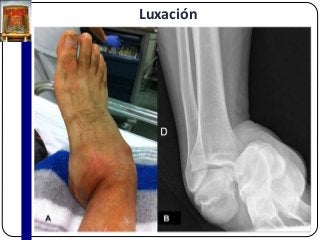

Luxación

 Pérdidas de las relaciones anatómicas de las

superficies articulares enfrentadas.

 Si la pérdida de la relación no es completa:

subluxación.

 Sus complicaciones agudas: compresión de

estructuras vasculares o nerviosas vecinas.

 Maniobras de reducción.